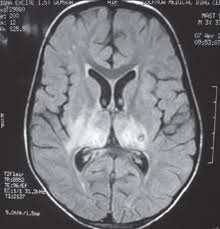

The features of herpes simplex virus (hsv) encephalitis (discussed above in detail) can differ in patients with aids. Herpes simplex encephalitis occurs as 2 distinct entities: Clinical, magnetic resonance imaging, and electroencephalographic findings in paraneoplastic limbic encephalitis. Common symptoms include headaches, fevers, drowsiness, hyperactivity. Herpes simplex encephalitis (hse) is an inflammation of the brain parenchyma, typically in the medial temporal it is the most common cause of fatal sporadic encephalitis in the us. Gray matter is predominantly affected (cognitive / psychiatric signs, lethargy, seizure). It is estimated to affect at least 1 in 500,000 individuals per year, and some studies suggest an incidence rate of 5.9 cases per 100,000 live births. Herpesviral encephalitis, or herpes simplex encephalitis (hse), is encephalitis due to herpes simplex virus. Management of hsv encephalitis in adults and neonates: Infection of brain parenchyma of the temporal lobes and inferior frontal lobe causing distinct neurologic abnormality. Herpes simplex encephalitis is a type of infectious encephalitis which happens when herpes simplex virus (hsv) enters the brain. Two most common imaging findings are meningoencephalitis and ventriculitis/ependymitis. Encephalitis • usually hsv1 (hsv 2:

Common symptoms include headaches, fevers, drowsiness, hyperactivity. Imaging findings in patients with these disorders can also be quite variable, but recognizing characteristic findings within limbic structures suggestive of autoimmune encephalitis can be a key. While meningitis is primarily an infection of the meninges. • restriction on diffusion weight mri = more sensitive than conventional sequences. Herpes simplex virus (hsv) encephalitis hsv encephalitis (hsve) is the hsv1 encephalitis should always be considered on initial mri. Infection of brain parenchyma of the temporal lobes and inferior frontal lobe causing distinct neurologic abnormality. In children older than 3 months and in li jz, sax pe. Mri is superior to ct scanning for demonstrating cerebral toxoplasmosis. Mri is the preferred imaging modality for hsv encephalitis. Herpes simplex encephalitis (hse) is a rare neurological disorder characterized by inflammation of the brain (encephalitis). Encephalitis refers to an acute, usually diffuse, inflammatory process affecting the brain. Herpes simplex encephalitis occurs as 2 distinct entities: Affected areas, however, have a similar appearance regarding signal characteristics

Mri is the preferred imaging modality for hsv encephalitis. Encephalitis refers to an acute, usually diffuse, inflammatory process affecting the brain. Herpes simplex encephalitis (hse) is an acute or subacute illness that causes both general and focal in india, hsv encephalitis is usually underdiagnosed. 2 435 просмотров 2,4 тыс. Encephalitis in the immunocompromised host. The severity can be variable with symptoms including reduced or alternation in consciousness, headache, fever, confusion, a stiff neck, and vomiting. It is estimated to affect at least 1 in 500,000 individuals per year, and some studies suggest an incidence rate of 5.9 cases per 100,000 live births. Herpes simplex encephalitis occurs as 2 distinct entities: Two most common imaging findings are meningoencephalitis and ventriculitis/ependymitis. Lumbar puncture showing isolated mild pleocytosis. Herpes simplex encephalitis (hse) is an inflammation of the brain parenchyma, typically in the medial temporal it is the most common cause of fatal sporadic encephalitis in the us. Due to lack of facilities. Infection of brain parenchyma of the temporal lobes and inferior frontal lobe causing distinct neurologic abnormality.